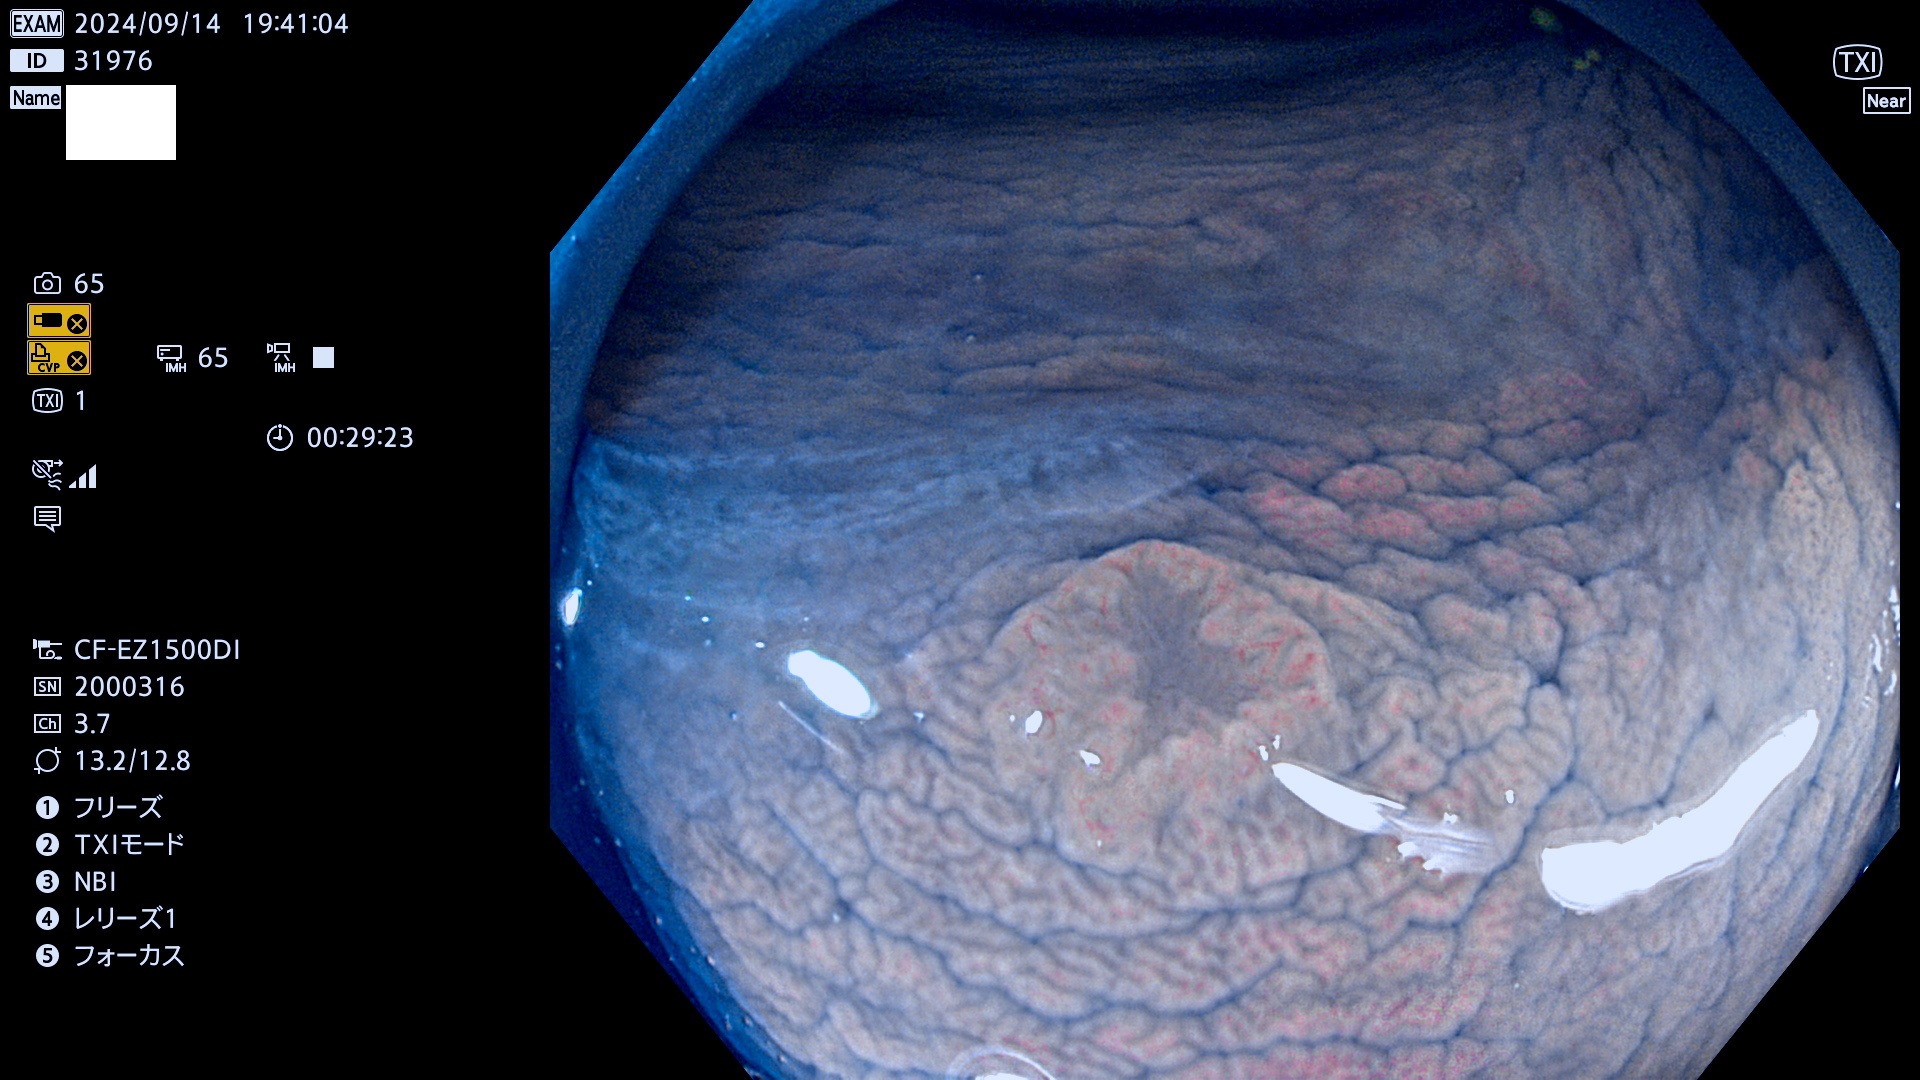

完全に平坦な物をUb、陥凹している物をUcと呼びます。最も発見が難しく危険な病変です。

毎週の検査(木・金・土・日)に発見されたUb、Uc型・腺腫を、その週の日曜の夜にUPし1週間、提示します。

抽出の対象期間 2024年9月12日〜9月15日の4日間(45件の検査)9件 (9/45=20%)